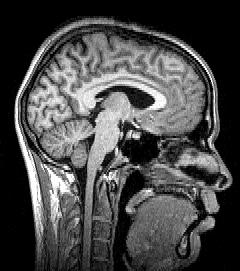

TÉCNICAS DE TOMOGRAFÍA COMPUTARIZADA Y ECOGRAFÍA

UT 1. Preparación de la exploración en TC.

UT 3. Realización de la exploración tomográfica.

UT 4. Obtención de la imagen en las exploraciones tomográficas.